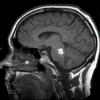

Cavernous Angioma (8)